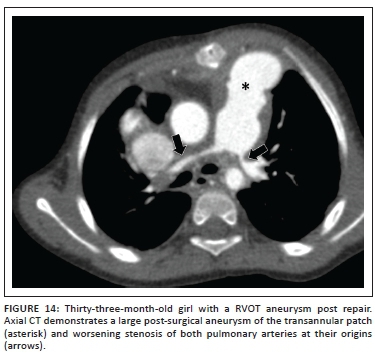

When the RVOT stenosis is more severe or involves the pulmonary valve annulus, a trans-annular patch repair, using treated pericardium or synthetic material to approximate the margins of the incision, is performed. The trans-annular anterior approach is associated with a variable amount of pulmonary valve insufficiency, resulting in eventual long-term RV dysfunction when excessive. Residual RVOT stenosis is implicated in the pathogenesis of the well-documented post repair complication of RVOT aneurysm (Figures 13-14). The ventriculotomy aneurysm may be complicated by the rare formation of intraluminal thrombus.16

Recurrent or residual stenosis of the main or branch pulmonary arteries can occur regardless of the type of surgery employed to relieve the RVOT obstruction (Figure 14). Serial imaging of the arteries may be needed to ascertain when intervention is required.